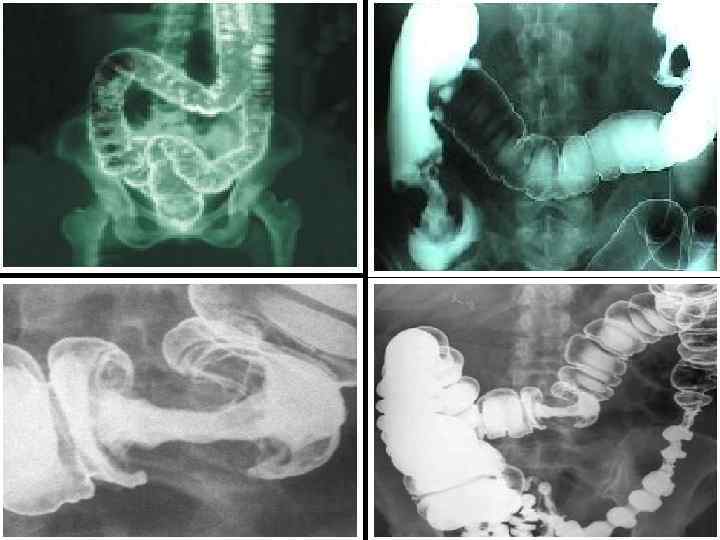

ИРРИГОСКОПИЯ